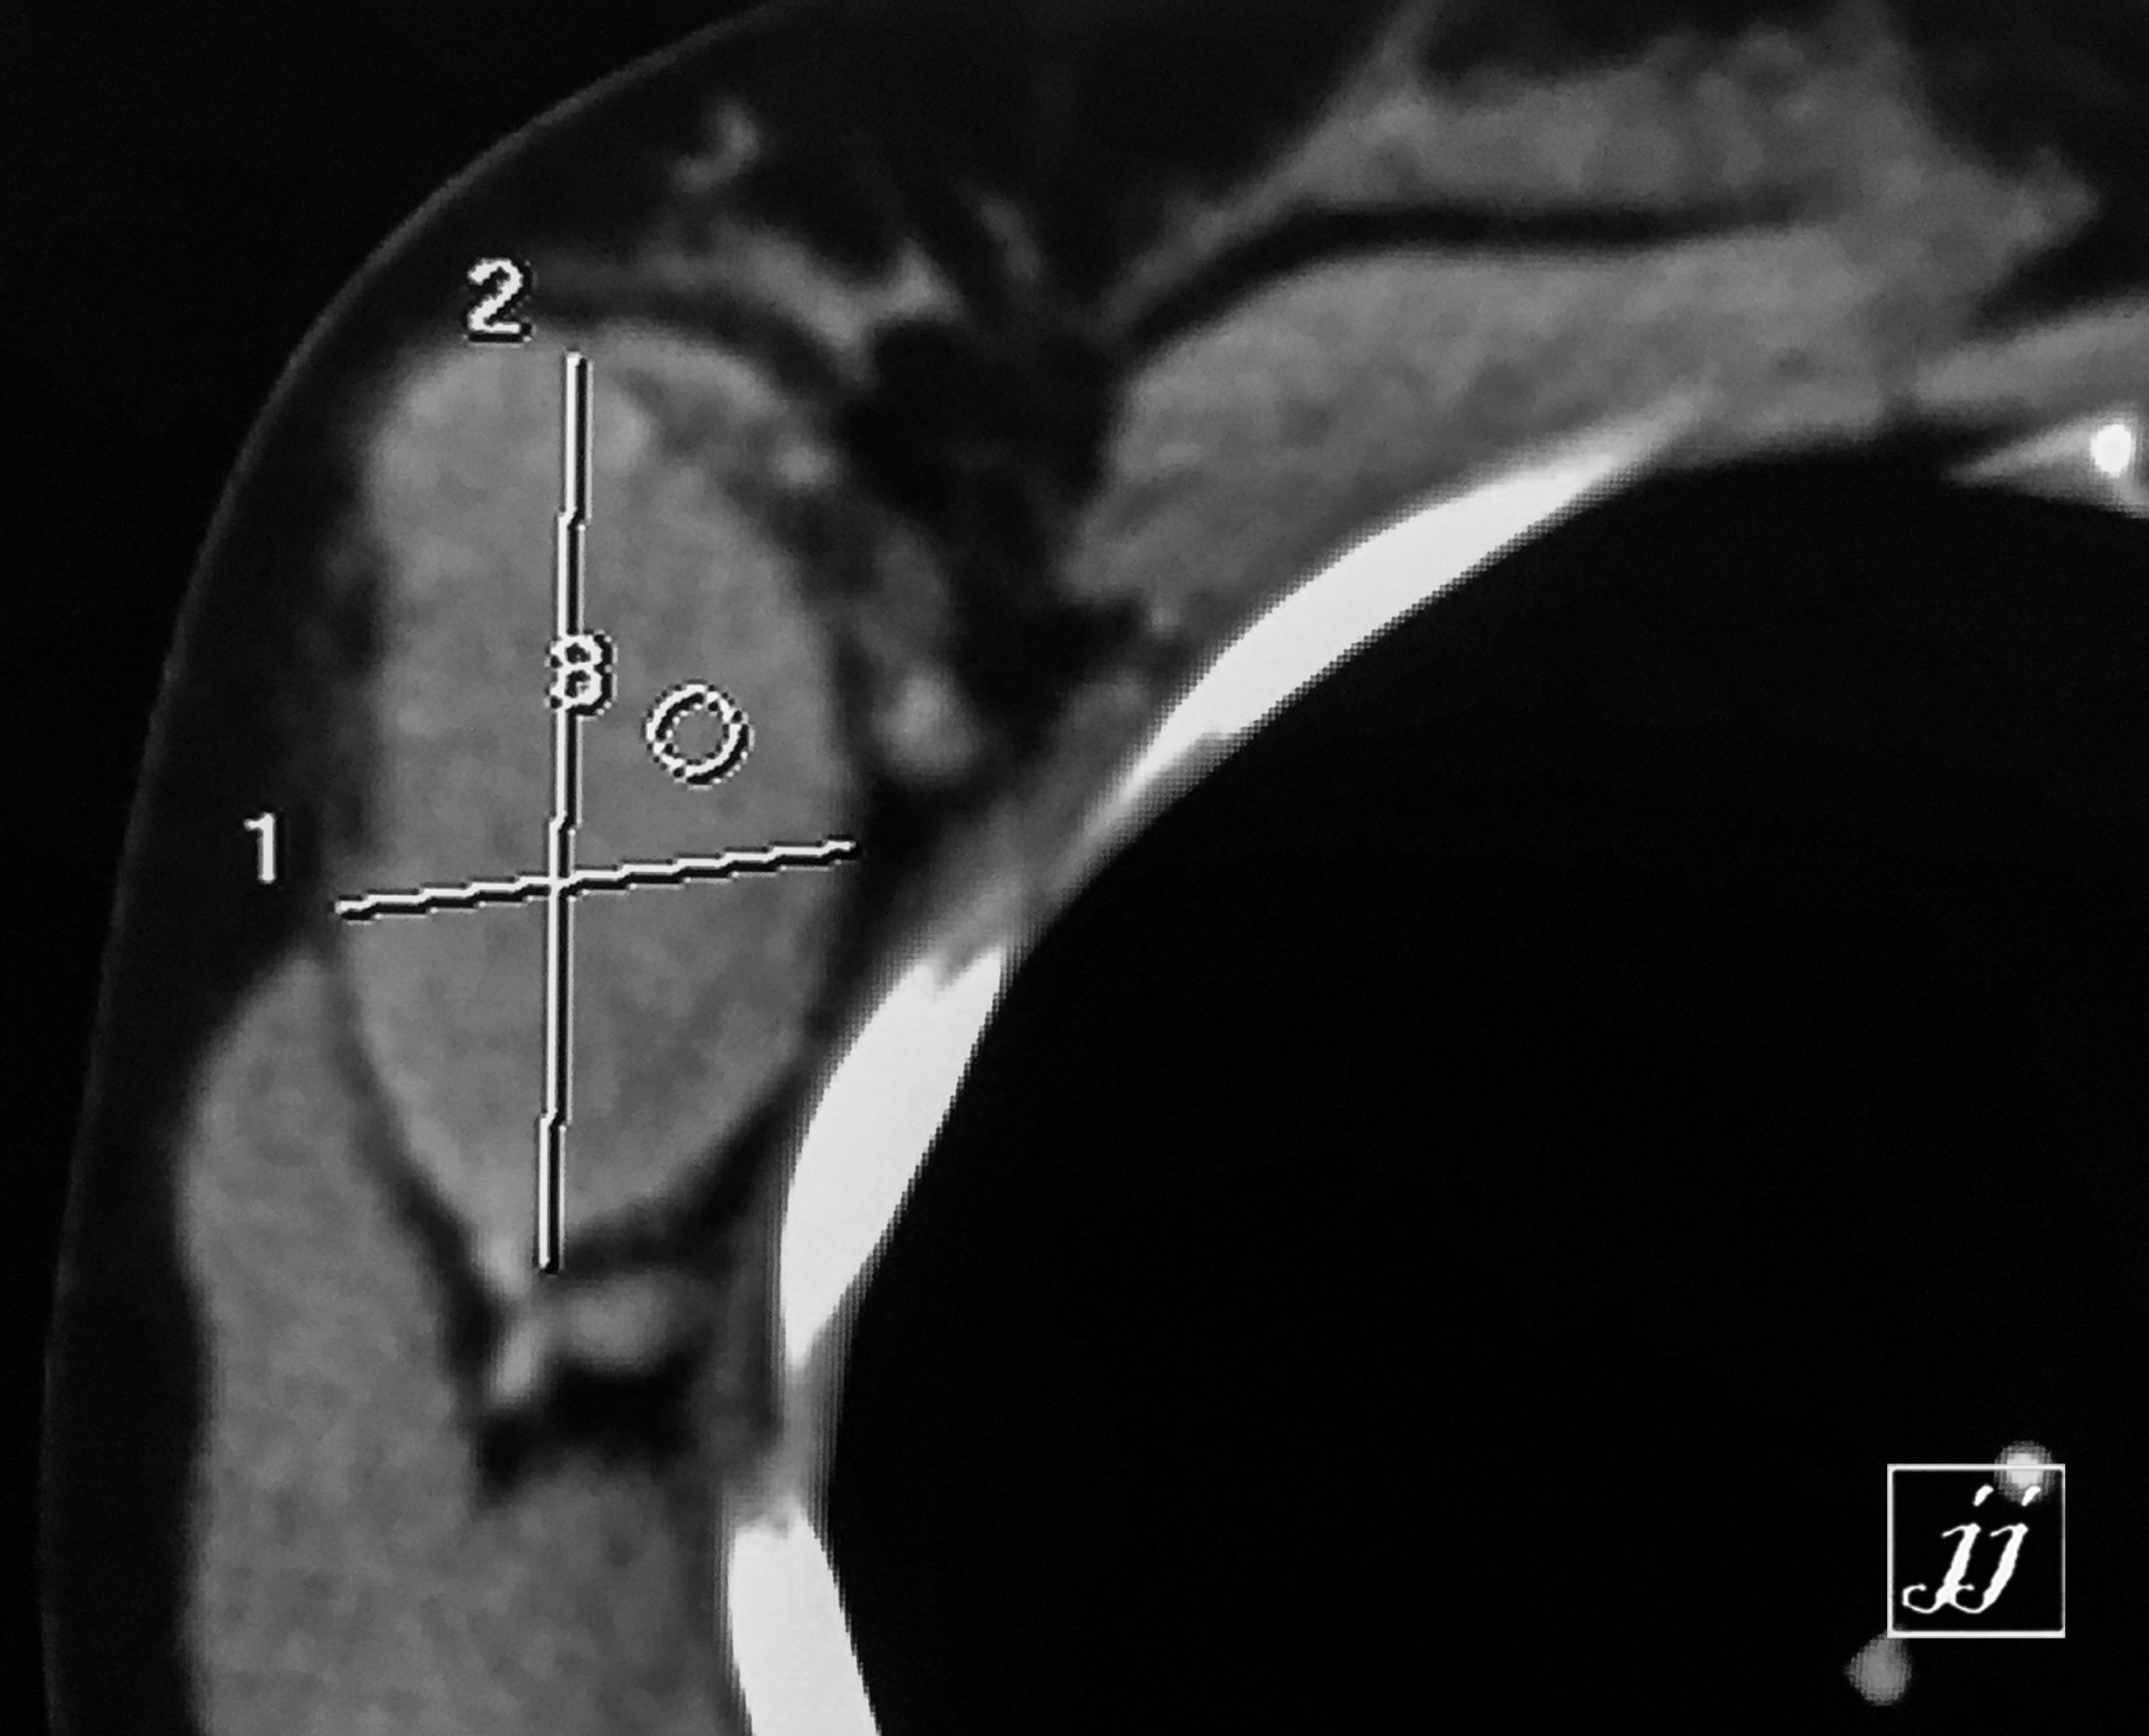

MSK- giant adenopathy of right axillary (3)